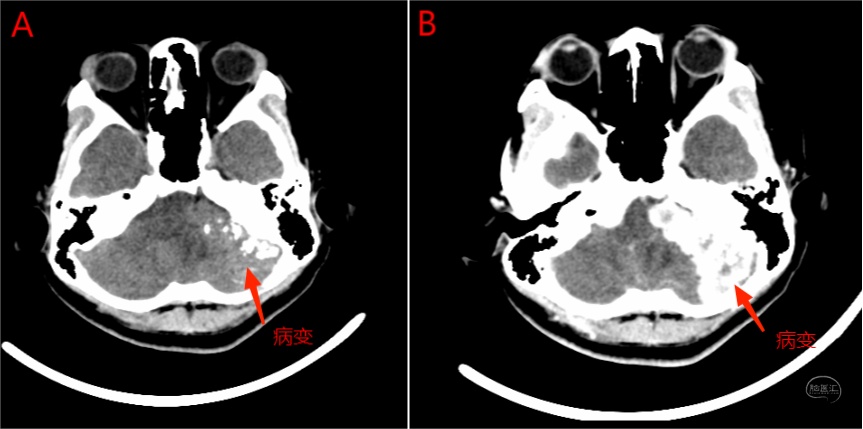

右侧颈静脉球瘤患者进行术前造影及栓塞,咽升动脉神经脑膜支(颈静脉孔支)为主要供血动脉。

图16 A图为轴位增强MRI,显示右侧颈静脉孔内病变强化明显;B图为TOF轴位图像,右侧咽升动脉神经脑膜支位于右侧颈内动脉后内侧,管径明显增粗(左侧显示不清)。